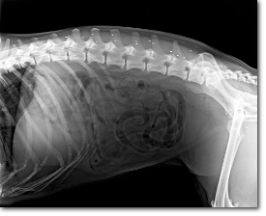

Zunächst werden eingehend die Probleme des Patienten aus Sicht des Besitzers erhoben, dann erfolgt eine sorgfältige Voruntersuchung bei der das Gangbild analysiert wird und die Schmerzpunkte, sogenannte Triggerpunkte ermittelt werden. Um ein Gesamtbild des Bewegungsapparates zu erhalten werden zusätzlich erforderliche Röntgenbilder digital angefertigt (ggf. erfolgen diese Aufnahme bereits in Sedation, z.B. Aufnahmen der Hüften).

Mittels einem speziell entwickelten Injektionsgerät werden nun die Goldimplantate an die Akupunkturpunkte z.B. direkt unter die Haut oder in die Muskulatur gesetzt. Diese Methode ist minimal invasiv und ist vergleichbar mit der Implantation eines Mikrochips.